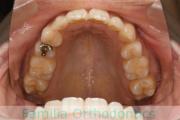

- ≫治療前

-

上顎

下顎

前歯の関係など

右側

正面

左側